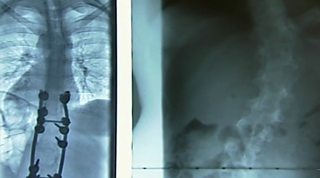

Kirsty Ashton's film follows the lives of those affected by neurofibromatosis.

Neurofibromatosis (NF), is a condition, which is not that well known or understood. I hope to make neurofibromatosis (NF) a household name, everyone has heard of cancer, and cystic fibrosis yet not many people will have heard of NF. It is as common as CF and can be very debilitating for the person who suffers from the condition.

Kirsty Ashton's film about the medical condition neurofibromatosis.